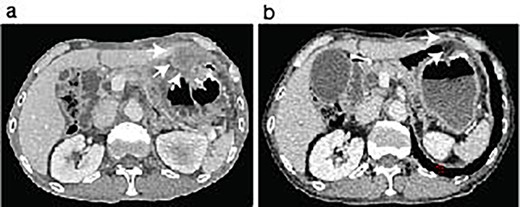

During the follow-up period, the patient presented with progressive anemia and general fatigue. Seven months after the lung surgery, the blood hemoglobin dropped to 6.8 mg/dl from 10.6 mg/dl at 2 months after the lung surgery. The patient was hospitalized, and a red blood cell infusion was performed. As fecal occult blood was consistently observed after the lung operation, another endoscopic examination of the upper and lower digestive tract was scheduled. In the meantime, the patient demonstrated a sudden onset of left side severe abdominal pain. The emergent enhanced CT scanning revealed a large abdominal mass in the left abdominal cavity (Fig. 2a). The subsequently performed small intestinal endoscopy revealed a tumor in the jejunum (Fig. 2b), and the biopsy of the tumor demonstrated the metastasis of the lung cancer. The partial resection of the jejunum including the metastatic lesion followed by end-to-end anastomosis was performed 8 months after the lung operation. The pathological diagnosis of the jejunum tumor was pleomorphic carcinoma, which was identical to the primary lung cancer (Fig. 2c-e). After 1 month of the second surgery, the patient again showed abdominal pain. The gastroscopy examination revealed a gastric tumor in the stomach wall with blood wheezing. Distal gastrectomy was performed 10 months after the lung operation. Some peritoneal nodules suspected of dissemination were also resected. The pathological diagnosis of the gastric tumor and peritoneal nodules was also pleomorphic carcinoma.

Identification of a metastatic intestinal tumor after lung surgery. An abdominal enhanced CT-scanning revealed a large mass lesion suggestive of small bowel involvement (a, arrows). A jejunum tumor was found in intestinal endoscopy (b). A surgical specimen of the metastatic lesion of the jejunum (c). H&E staining of the jejunum tumor showed submucosal malignant cells (d) with pleomorphic features compatible with the primary pleomorphic lung carcinoma (e).